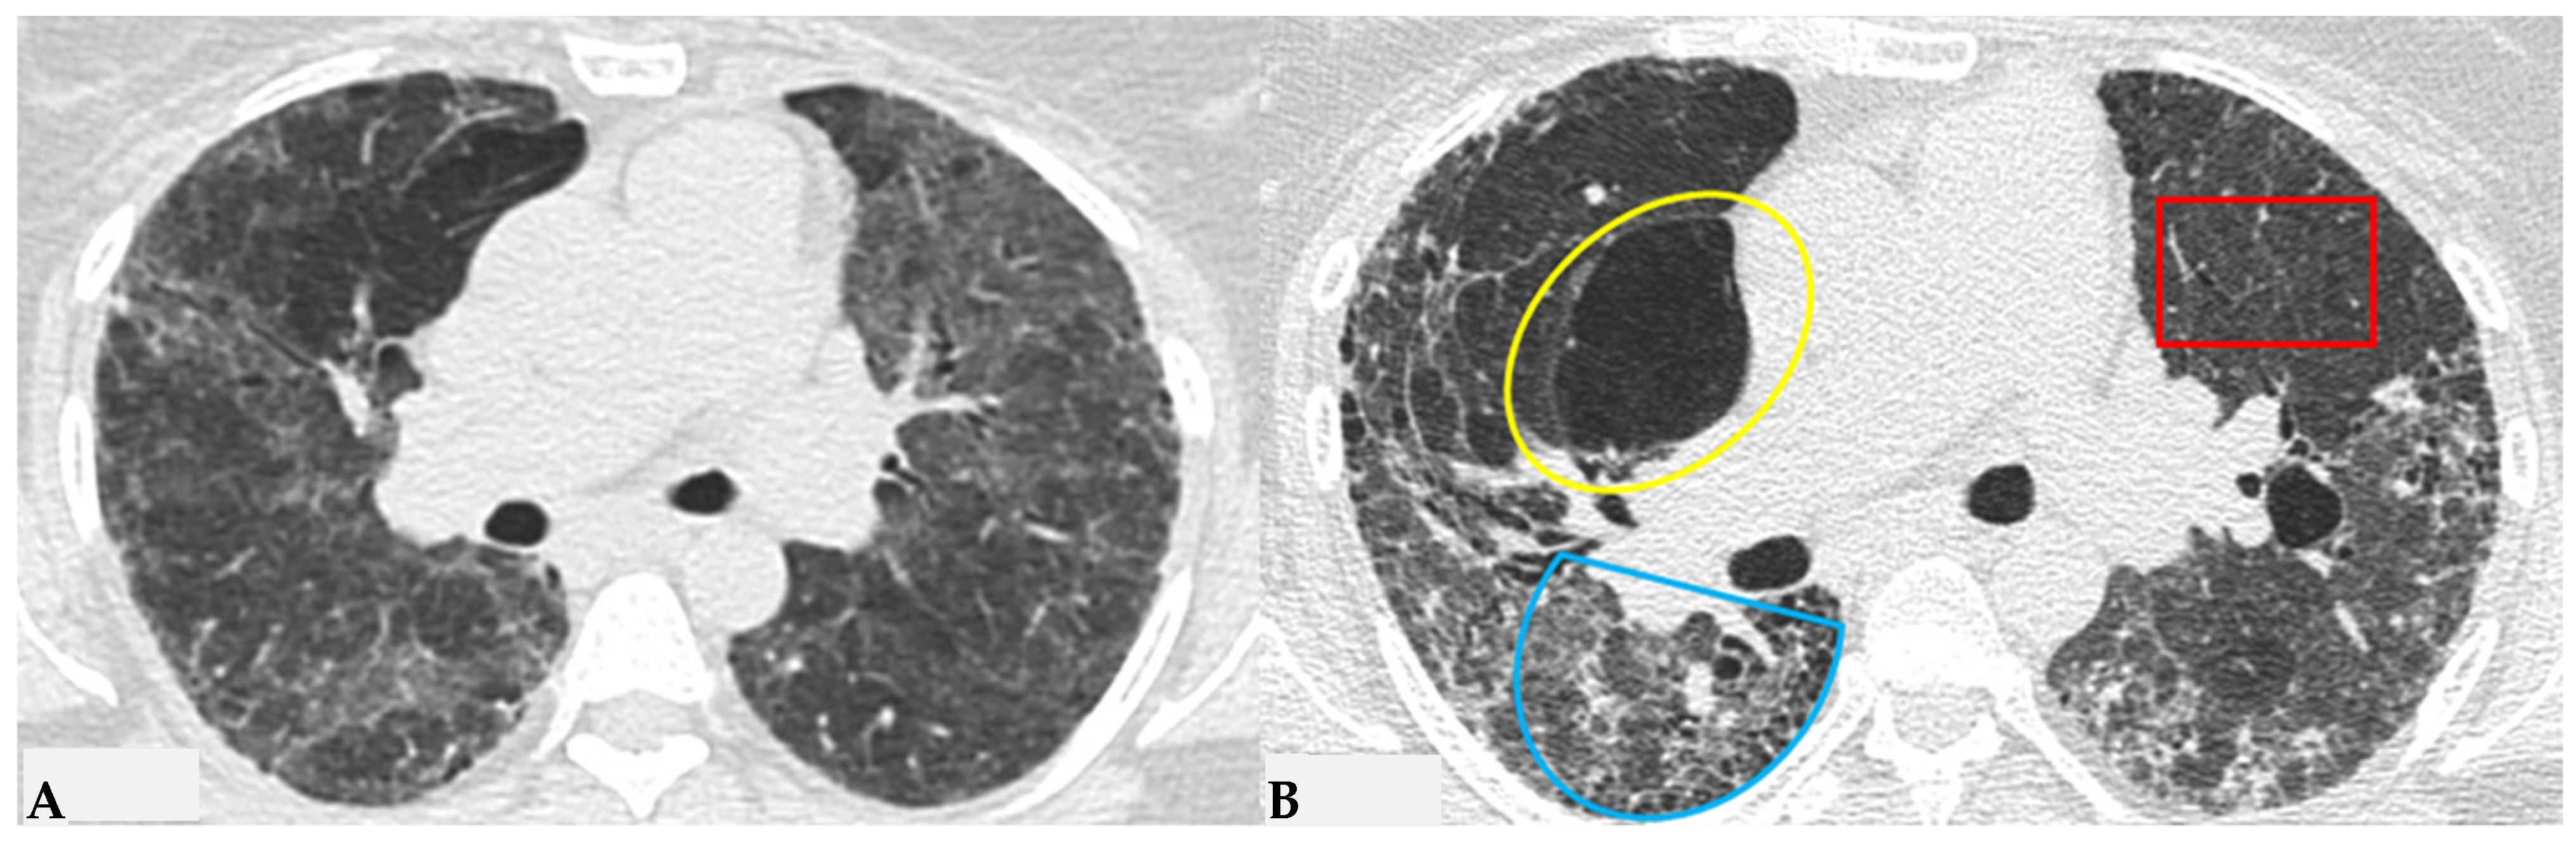

The fibrotic damage in HP is often more severe and extensive in the middle or middle-lower lung zones, but at times, it can be equally distributed across all three lung zones with relative sparing of the subpleural compartment, presenting a “patchy” distribution as a trace of a previous inhalation-mediated immune attack. This distribution may not always exhibit a clear central or peripheral predominance, as evident in axial assessments or MPR reconstructions [7,8,9]. The obstruction of small airways, another significant and distinctive feature of HP, can manifest with various characteristics. In (NFHP), poorly defined centrilobular nodules (fluffy nodules) and mosaic attenuation can be observed. The corresponding HRCT semiotics in FHP presents a “three-density pattern” (Figure 5), characterized by the simultaneous presence of pulmonary lobules with normal density, lobules with (GGO) and lobules with reduced density and size of vascular structures (mosaic attenuation/air trapping) due to air entrapment resulting from broncho-obstruction (Figure 6). The three-density pattern becomes more evident in expiratory HRCT scans due to the air entrapment resulting from the pathogenesis of bronchiole obstruction [4,10].

Figure 5.

FHP: chest HRCT ((A,B): axial scan). Visible is the “three density pattern”, with areas of the lung with normal density spared from pathological changes (red box); areas of the lung with reduced density characterized by a paucity of vascular and bronchial structures (yellow box); areas of the lung with increased density showing reticulations, interstitial thickening and traction bronchiectasis (green box). Lung cyst (red arrow) and areas of smoking-related paraseptal emphysema and advanced destructive emphysema (ADE) (blue arrows) are also present.

Figure 6.

HRCT of the chest and magnification areas of RLL and LUL in FHP. Three-density pattern with lobular areas of reduced attenuation in both lungs (magnification images), overlapping with areas of increased density where distinct fibrotic alterations are evident, characterized by intra- and inter-lobular thickening with traction bronchiectasis and bronchiolectasis (red box). In certain patients, the absence of typical HRCT fibrotic features leads to their classification as “pattern compatible with FHP”. Suggestive elements of this pattern are fibrosis with a mixed central and peripheral distribution (Figure 7) and the fibrotic pattern with basal predominance (Figure 8).